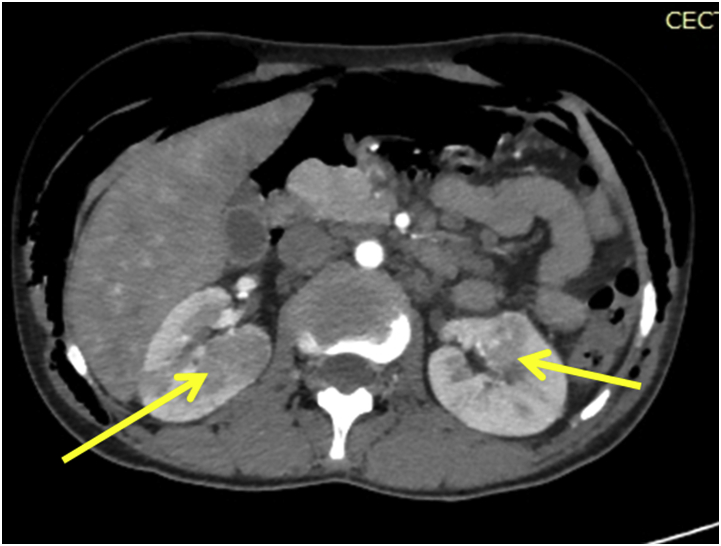

He was evaluated further. Fundoscopic examination of the eye revealed multiple astrocytomas. CECT abdomens showed well defined heterogeneously enhancing lesions in the right kidney suggestive of angiomyolipoma (Fig. 5).

Fig. 5.

CECT abdomens showed well defined heterogeneously enhancing lesions in the right kidney suggestive of angiomyolipoma.